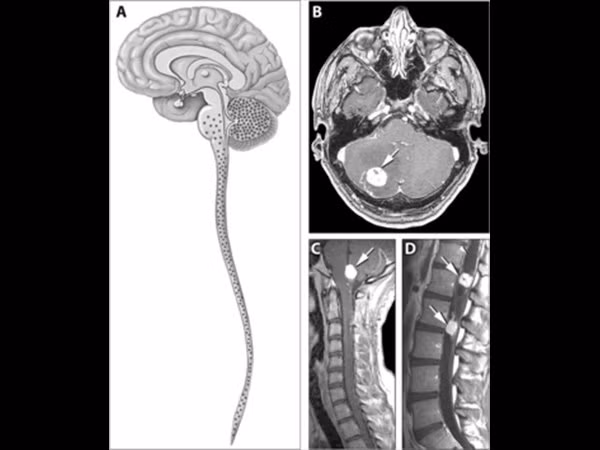

Bệnh Von Hippel-Lindau (VHL) gây ra khối u phát triển khắp cơ thể, đặc biệt là ở hệ thần kinh trung ương (não và tủy sống). Và mặc dù những khối u này có tính chất lành tính, nếu không được điều trị, chúng có thể gây đột quỵ hoặc đau tim, dẫn đến tử vong.